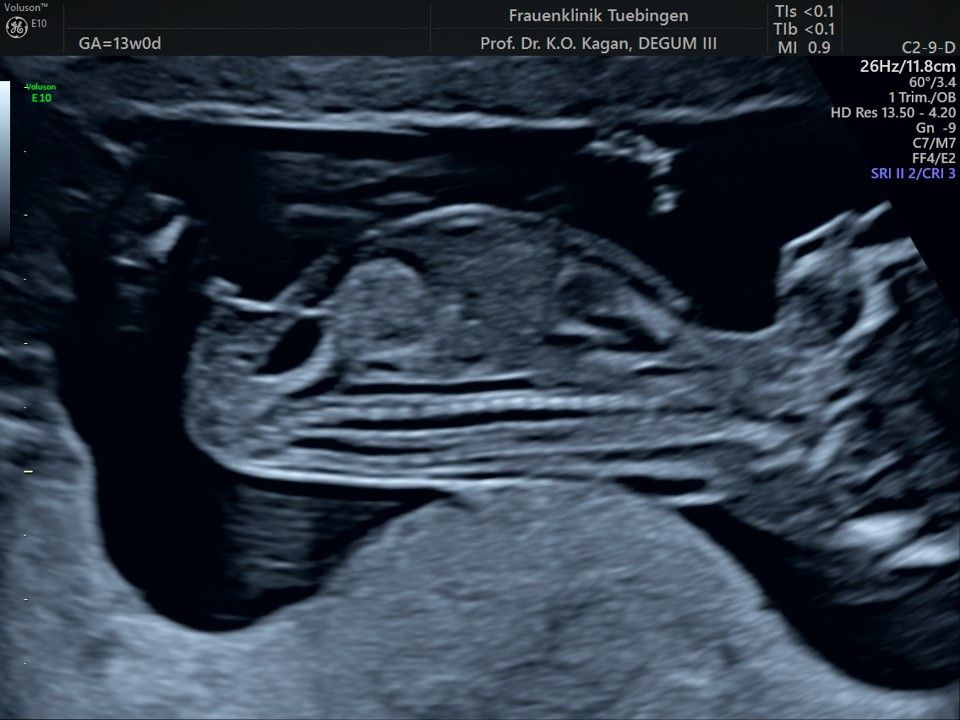

Im Rahmen des Ersttrimester-Screenings untersuchen wir die Organe des Feten mittels Ultraschall. Dabei machen wir auch gerne ein Bild für Sie.

Obwohl der Fet zu diesem Zeitpunkt erst zwischen 5 und 8cm groß ist, lassen sich bereits etwa die Hälfte aller schwerwiegenden Fehlbildungen erkennen bzw. ausschließen. Sollten wir eine Auffälligkeit sehen, werden wir mit Ihnen den Befund und das weitere Vorgehen ausführlich besprechen.

Fetale Anatomie